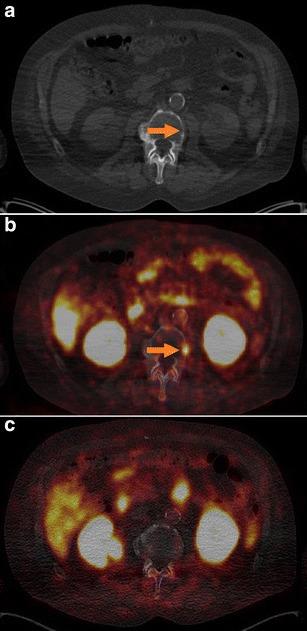

In 14 selected patients with PSA relapse of prostate cancer, [(18)F]DCFPyL PET/X-ray computed tomography (CT) was performed in addition to [(68)Ga]Ga-PSMA-HBED-CC PET/CT. A systematic comparison was carried out between results obtained with both tracers with regard to the number of detected PSMA-positive lesions, the standardized uptake value (SUV)max and the lesion to background ratios.

RESULTS

All suspicious lesions identified by [(68)Ga]Ga-PSMA-HBED-CC were also detected with [(18)F]DCFPyL. In three patients, additional lesions were observed using [(18)F]DCFPyL PET/CT. The mean SUVmax in the concordant [(18)F]DCFPyL PSMA-positive lesions was significantly higher as compared to [(68)Ga]Ga-PSMA-HBED-CC (14.5 vs. 12.2, p = 0.028, n = 15). The mean tumor to background ratios (n = 15) were significantly higher for [(18)F]DCFPyL compared to [(68)Ga]Ga-PSMA-HBED-CC using kidney, spleen, or parotid as reference organs (p = 0.006, p = 0.002, p = 0.008), but no significant differences were found using the liver (p = 0.167) or the mediastinum (p = 0.363) as reference organs.

在14例选定的前列腺癌PSA复发患者中,除了进行[(68)Ga]Ga-PSMA-HBED-CC PET/CT外,还进行了[(18)F]DCFPyL PET/X射线计算机断层扫描(CT)。对两种示踪剂获得的结果在检测到的PSMA阳性病变数量、标准化摄取值(SUV)最大值和病变与背景比值方面进行了系统比较。

结果

[(68)Ga]Ga-PSMA-HBED-CC识别出的所有可疑病变也能用[(18)F]DCFPyL检测到。在3例患者中,使用[(1)F]DCFPyL PET/CT观察到了额外的病变。与[(68)Ga]Ga-PSMA-HBED-CC相比,[(18)F]DCFPyL PSMA阳性病变中的平均SUV最大值显著更高(14.5对12.2,p = 0.028,n = 15)。以肾脏、脾脏或腮腺作为参考器官时,[(18)F]DCFPyL的平均肿瘤与背景比值(n = 15)显著高于[(68)Ga]Ga-PSMA-HBED-CC(p = 0.006,p = 0.002,p = 0.008),但以肝脏(p = 0.167)或纵隔(p = 0.363)作为参考器官时未发现显著差异。